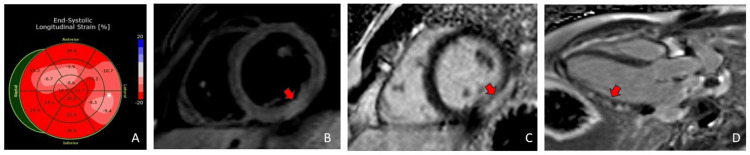

A 20-year-old man without a significant past medical history presented with substernal chest pain that worsened with deep inspiration and radiated to the left jaw and neck for the past six hours. Vital signs were normal. The urine drug screen was positive for cocaine and cannabinol. He acknowledged cocaine use, and his most recent use was two days prior. Peak troponin I was 52 ng/mL (normal 0.00-0.09 ng/mL). The electrocardiogram (ECG) showed diffuse ST-segment elevation (Figure 1).

The transthoracic echocardiogram (TTE) demonstrated a normal left ventricular size and function with an ejection fraction of 55-60% and normal global longitudinal strain of -17.4% (normal -17% to -24% for males) but with diminished absolute values in the lateral wall (Figure 2). He underwent a coronary angiogram (CAG) for persistent chest pain that did not show angiographic evidence of coronary artery disease. He then underwent a CMR to evaluate for a non-ischemic cause of his myocardial injury. CMR demonstrated inferolateral hyperintensity on T2-weighted imaging consistent with edema. There was associated meso- and subepicardial gadolinium delayed enhancement at the same segment. Findings were most consistent with acute myocarditis (Figure 2).